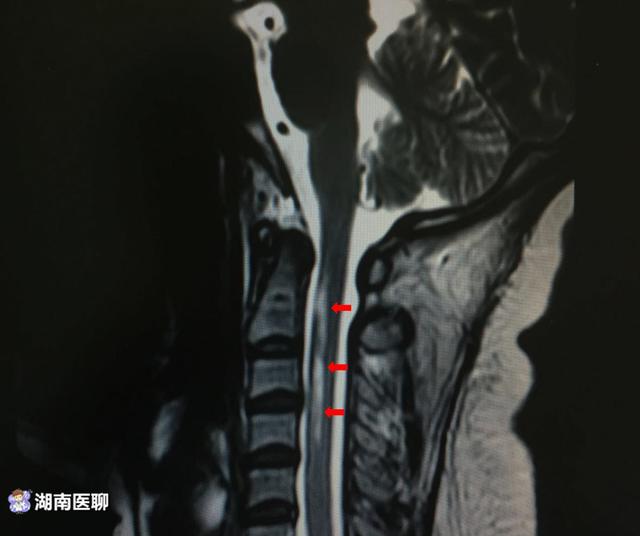

(颈部前侧异常信号提示脊髓病变,箭头处)

(脊髓横截面脊髓前部异常信号)

发现高位颈髓出现明显异常信号,并且患者右侧存在视神经异常信号。

患者入院后有明显呼吸困难,黄晓松教授考虑呼吸困难与高位颈髓病变有关。

并根据病史,考虑患者颈髓病变脱髓鞘疾病,视神经脊髓炎可能性较大,需要予以大剂量激素冲击治疗,并且予以无创呼吸机辅助呼吸治疗。